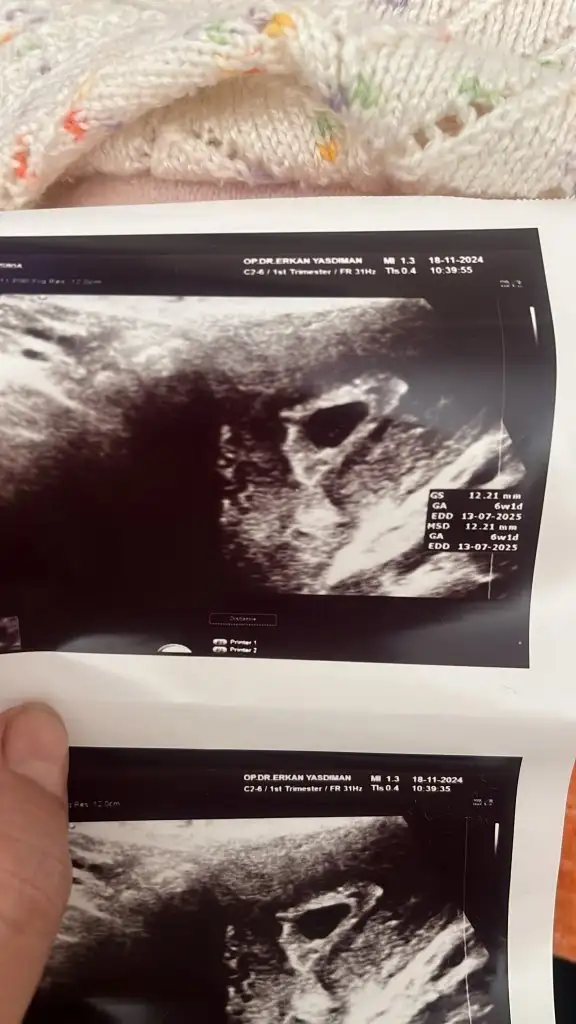

Canım yeni geldim doktordan karından bebegi ve kalp atışını gördük kanamam hala var biraz çogaldı 5 tane igne yazdı yolk kesesi felan oluşmuş ama bebek minnacık daha ilk attıgım ilk gittigim vajinal digeri karından karından bebek görüldü